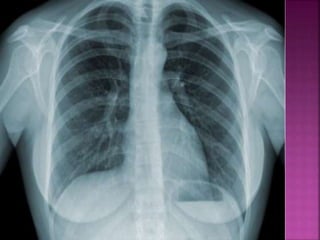

• A tuberculose é uma doença infecto-

contagiosa causada por uma bactéria

que afeta principalmente os pulmões,

mas também pode ocorrer em outros

órgãos do corpo, como ossos, rins e

meninges (membranas que envolvem o

cérebro).